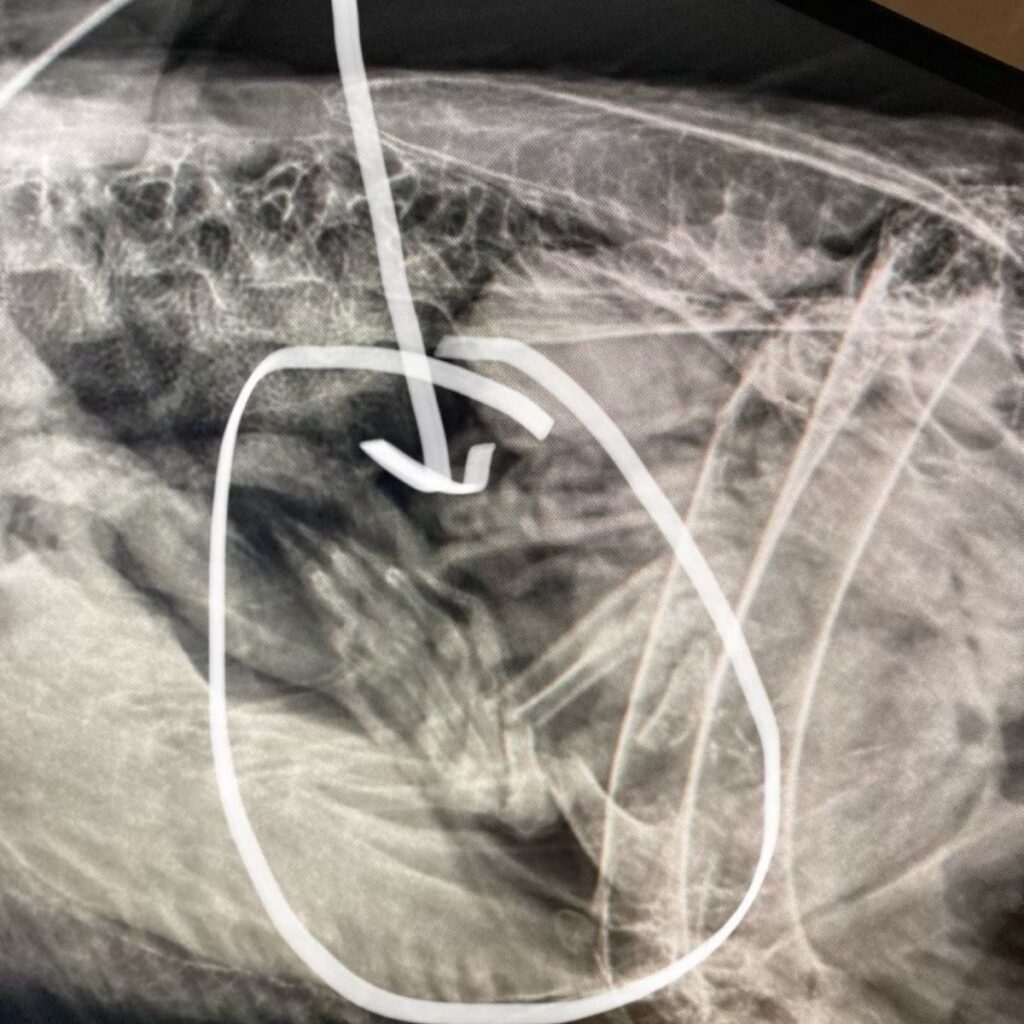

To get answers, the bird was taken to Dickerson Park Zoo for X-rays. That’s when the mystery was solved, and the entire team burst out laughing.

The x-ray showed something unmistakable: the paws of a raccoon sitting inside his very full stomach. The bird had indulged in such an oversized meal that flying was out of the question.